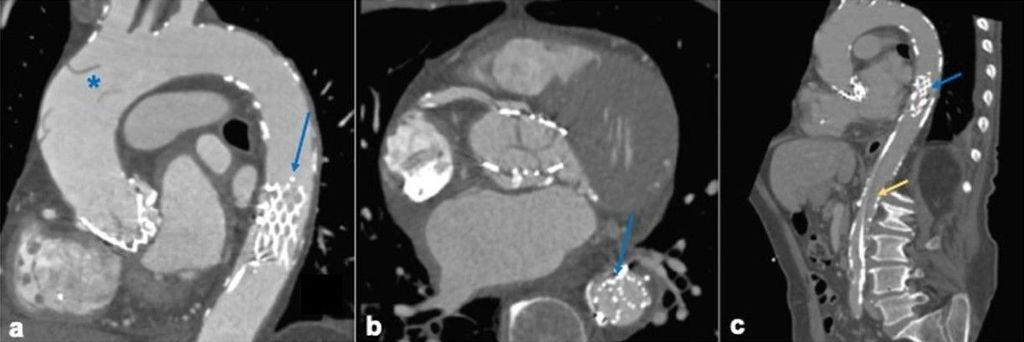

Bệnh viện Đa khoa Tâm Anh TP.HCM chính thức làm chủ kỹ thuật TAVI – cấy van động mạch chủ qua ống thông, trở thành Trung tâm độc lập thực hiện kỹ thuật này sau khi được 2 tập đoàn y khoa hàng đầu Hoa Kỳ công nhận. Kỹ thuật TAVI là can thiệp tim mạch cấp cao, ít xâm lấn, giúp bệnh nhân hẹp van động mạch chủ nặng tránh phẫu thuật mở tim. Thành tựu đạt được chỉ trong 4 tháng thể hiện bước tiến mạnh mẽ của y học Việt Nam.